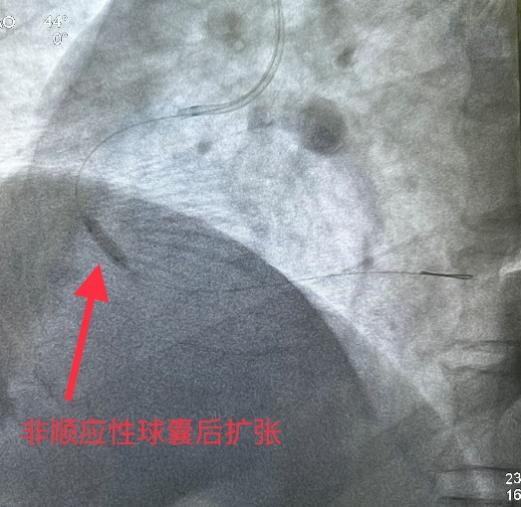

5月31日经过充分的术前准备,雷新军教授带领景林德博士和李瑞峰医生按照预定方案为患者实施了手术。冠脉造影示:RCA 2段节段性狭窄约25%,末端狭窄约90%,为不稳定斑块,血流TIMI 3级(图2a)。决定干预右冠:6F SAL1.0指引导管到位后,先操控Sion导丝通过病变至LV末端,然后再沿导丝送入血管内超声(intravenous ultrasound,IVUS)检查,结果显示RCA 2段末狭窄最重部位血管面积为2.30 mm2,斑块负荷为85%,手术指征明确(图2b)。首先,使用NC Balloon 3.0 x 15 mm 20 atm预扩张靶病变,造影示残余狭窄约25%,再在IVUS指导下植入Xinsorb BRS 3.5 x 28 mm,随后采用NC Balloon 3.5 x 9 mm 16atm逐段后扩张,造影显示支架充分膨胀,血流TIMI 3级(图2c-g)。最后,进一步使用IVUS评估手术情况,结果显示:支架充分膨胀,贴壁良好,支架远近端未见夹层,血管面积为8.01 mm2,手术效果非常满意(图2h)。术中患者无特殊不适,术后病人安返病房。

图2 经皮冠脉介入治疗